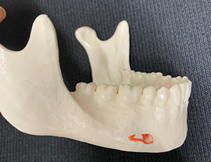

ご自身に合っていない義歯や、強度が足りずたわんでしまうような義歯を装着していると、その代償としてご自身の顎骨(歯肉)が、やせていくことが分かっています。

これは急速に進行するわけではないので、ご自身では自覚はありません。

義歯が安定しなくなった時点で自覚され、そして新しく義歯を作り直そうと思われても、その時は単に新製しても問題が解決せず、以前になかった義歯の問題が噴出するということはよくあります。

知らない間に、一度やせてしまった顎骨は増えることはありません。

顎骨がやせた場合は、義歯の難症例となり、治療自体も妥協的に終了せざるを得ない場合も増えてきます。

精密義歯治療で用いる治療用義歯は、ご自身の顎骨、歯肉への将来的な負担を減らす目的で 使用します。

負担が減れば、最終的に製作する精密義歯も成功率が上がり、かつより長く使って頂ける可能性が高まります。